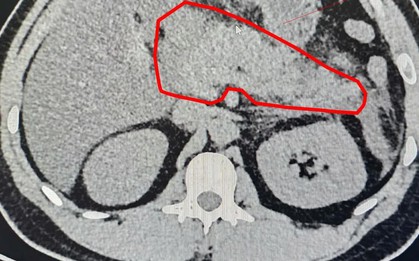

Nhập viện trong tình trạng đau bụng dữ dội vùng thượng vị, buồn nôn, bụng chướng nhiều… ông N.V.C (47 tuổi, Phú Thọ) được chẩn đoán viêm tụy cấp. Đáng chú ý, từ năm 2020 đến nay, người bệnh có thói quen uống rượu mỗi ngày từ 300-500ml.